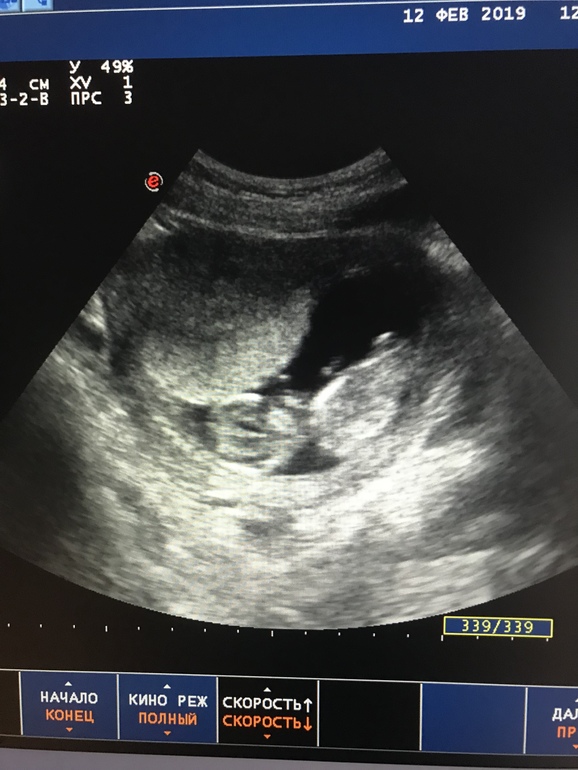

Тонус ПЛАЦЕНТЫ +УЗИ 12 недель . 🙏🏻У кого так же было?

Результаты: УЗИ, КТГ, доплера, скринингаПодскажите, кому ставили ТОНУС В ОБЛАСТИ ПЛАЦЕНТЫ на задней стенке? Гинеколог сказала что это плохо. Как бы угроза.

Сердцебиение 164 уд./мин. Диаметр ПЯ 8см, КТР 6 см.

Я просто переживаю Что по снимку УЗИ , видно что тонус в области плаценты и как бы уже почти до ребёнка достаёт

У вас также тонус на УЗИ видно было??

Я переживаю что на моем снимке плацента в тонусе и достаёт уже до головы ребёнка

У меня тонус был похожий в 15 недель где то. По задней и передней стенке.

Я в больницу легла, потому что на УЗИ было прекрасно видно как моего ребёнка сдавливают стенки матки. И я не думаю что это хорошо.

Картина была точь в точь как у Вас, я даже спросила, что это за надутый шарик)), тоже по задней стенке и тоже где плацента.Меня даже никто и не думал пугать этим, сказали норма, что это реакция на волнения, датчик и тп, что если бы я полежала 5 мин, то мышца матки пришла бы в норму, ничего не пила и ничего мне и не рекомендовали пить. Сегодня (спустя) 2 недели была на узи шейки матки, уже никакого тонуса не было. (Специально просила посмотреть).